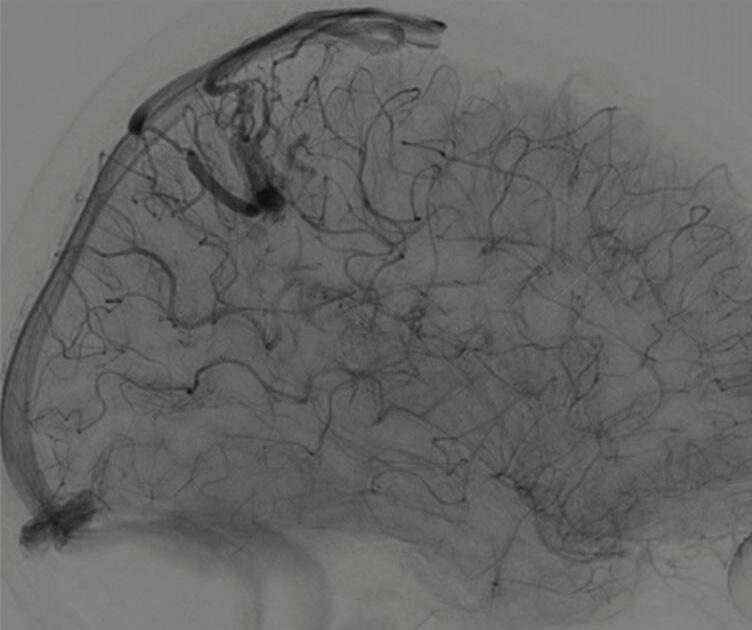

Fig. 1-9. RNM T2 em cortes (a) axial e (b) sagital. (c,d) Tractografia axial – sagital, demonstrando a posição de uma MAV não rota localizada na superfície basal do lobo frontal, nos giros orbitários e reto à direita (setas longas). Arteriografia digital cerebral com injeção de contraste via carótida direita, (e) AP e (f) em perfil demonstrando MAV nutrida por ramos da artéria cerebral média e cerebral anterior direita e drenagem para o seio sagital superior (seta curta).